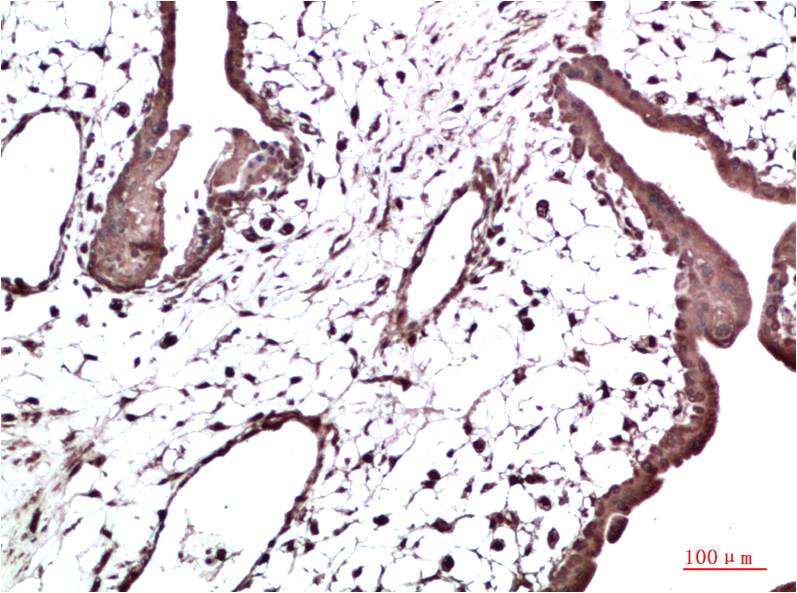

HP-1γ Mouse Monoclonal Antibody(2F5)

Catalog NO.:BE3695

Applications :WB, IHC

Reactivity :H,R,M

Recommended dilutions: WB 1:1,000-2,000 IHC 1:100-200

Specificity: The HP-1γ Mouse Monoclonal Antibody can detects endogenous HP-1γ proteins.